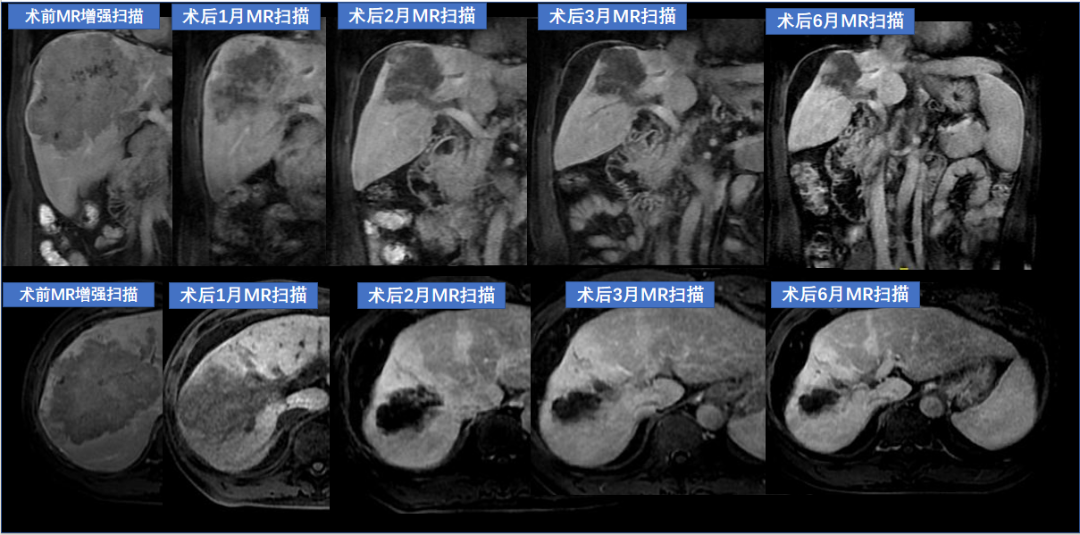

肝巨大肿瘤合并门静脉瘤栓

肝右叶巨块占位15.7cm,Child分级B级 7分,PS评分0分,少量腹水,AFP:5225ng/ml,PIVKV-II 22966.4mAU/ml,门脉癌栓形成,腹腔淋巴结转移,诊断 HCC CNLC分期 IIIb

术后随访1~6个月